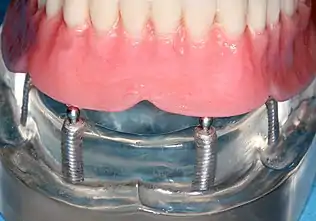

Implant-supported overdenture

A removable implant supported denture (also an implant supported overdenture[17]: 31 ) is a removable prosthesis which replaces teeth, using implants to improve support, retention and stability. They are most commonly complete dentures (as opposed to partial), used to restore edentulous dental arches.[11] The dental prosthesis can be disconnected from the implant abutments with finger pressure by the wearer. To enable this, the abutment is shaped as a small connector (a button, ball, bar or magnet) which can be connected to analogous adapters in the underside of the dental prosthesis.

Prosthetic procedures for removable dentures

When a removable denture is worn, retainers to hold the denture in place can be either custom made or "off-the-shelf" (stock) abutments. When custom retainers are used, four or more implant fixtures are placed and an impression of the implants is taken and a dental lab creates a custom metal bar with attachments to hold the denture in place. Significant retention can be created with multiple attachments and the use of semi-precision attachments (such as a small diameter pin that pushes through the denture and into the bar) which allows for little or no movement in the denture, but it remains removable.[17]: 33–34 However, the same four implants angled in such a way to distribute occlusal forces may be able to safely hold a fixed denture in place with comparable costs and number of procedures giving the denture wearer a fixed solution.[53]

Alternatively, stock abutments are used to retain dentures using a male-adapter attached to the implant and a female adapter in the denture. Two common types of adapters are the ball-and-socket style retainer and the button-style adapter. These types of stock abutments allow movement of the denture, but enough retention to improve the quality of life for denture wearers, compared to conventional dentures.[54] Regardless of the type of adapter, the female portion of the adapter that is housed in the denture will require periodic replacement, however the number and adapter type does not seem to affect patient satisfaction with the prosthetic for various removable alternatives.[55]